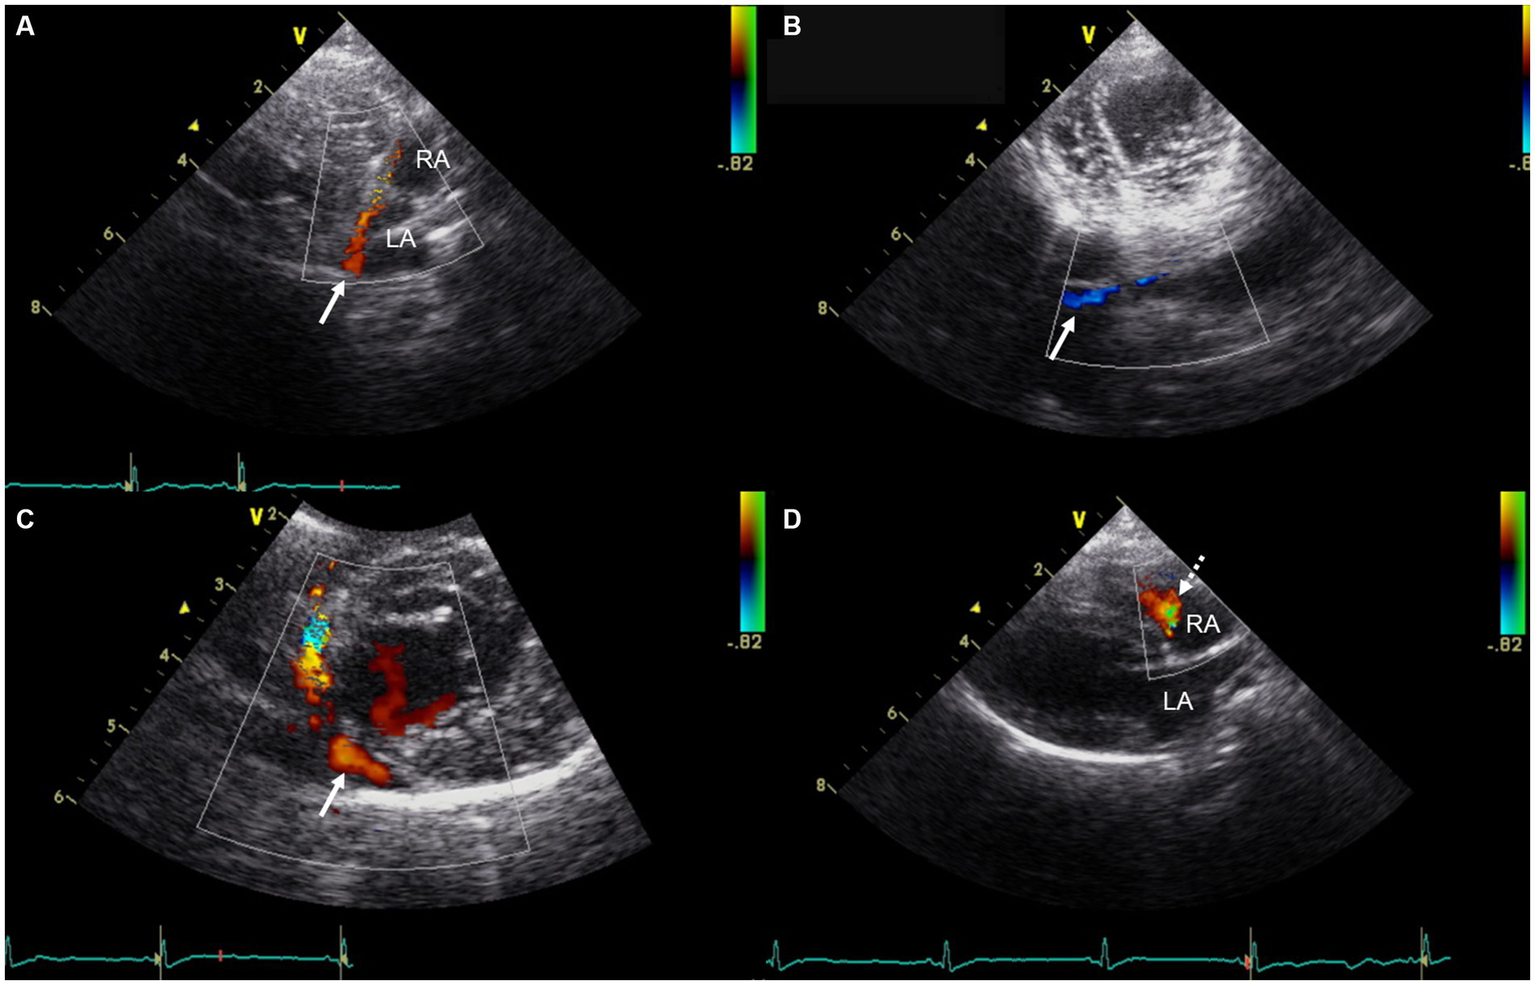

Transthoracic echocardiography (GE Vivid 7, Horten, Norway) using a 5-MHz transducer identified a LA size at the upper limit of the normal range, with a left atrium-to-aortic root ratio of 1.7 (upper reference limit: 1.62–1.83) (13). The left ventricle, right atrium (RA) and right ventricle appeared normal in size. There was no evidence of pulmonary hypertension, systolic dysfunction, or diastolic dysfunction. Color Doppler imaging identified a markedly visualized tubular structure running along the posterior aspect of the LA and extending caudally to the RA near the tricuspid valve annulus, which was presumed to be the coronary sinus. Color Doppler imaging demonstrated a continuous blood flow of unclear origin into the RA, with a velocity of 0.5 m/s (Figure 2). No atrial septal defect was identified. The pulmonary-to-systemic blood flow ratio (Qp/Qs) was 1.3 (reference range: 0.71–1.29) (14). Contrast-enhanced echocardiography using hand-agitated saline confirmed the absence of an intracardiac right-to-left shunt. As the origin of the continuous blood flow into the right atrium was not clearly identified on echocardiography, additional CT (SIEMENS Healthineers, Erlangen, Germany) was performed to differentiate potential congenital cardiac anomalies that could cause continuous shunting into the right atrium, such as UCS, coronary artery fistula, or partial or total anomalous pulmonary venous connection (5, 15, 16).

Figure 2. Transthoracic echocardiographic images showing a markedly visualized coronary sinus and continuous blood flow into the right atrium. (A) Modified right parasternal long-axis view. (B) Modified left apical four-chamber view at the level of the chordae tendineae. (C) Modified right parasternal short-axis view. (D) Right parasternal long-axis four-chamber view. In panels (A–C), Color Doppler imaging identified a markedly visualized tubular structure (white arrow) running along the posterior aspect of the LA and extending caudally to the RA, near the tricuspid valve annulus, which is presumed to represent the coronary sinus. In panel (D), Color Doppler imaging demonstrates continuous blood flow (white dashed arrow) of unidentified origin entering the RA. LA, left atrium; RA, right atrium.